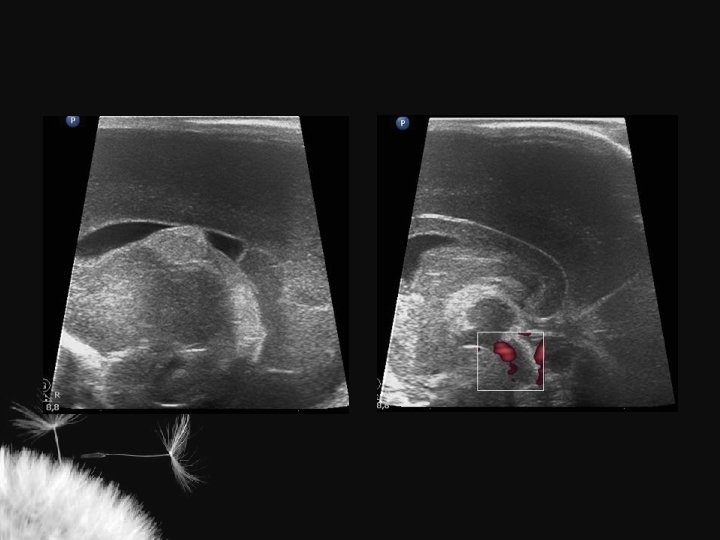

VENTRICULOMEGALIA

LESÃO HIPÓXICO-ISQUÊMICA NO RN TERMO